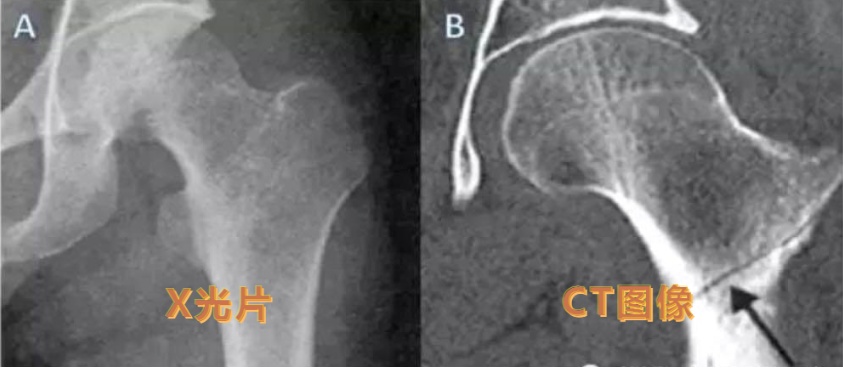

然而,正如前面介绍的,普通x线检查有一个很突出的缺点,就是它只能显示照射范围内所有器官重叠在一起的影子,无法将其区分开,容易误诊、漏诊。而CT、MRI检查则能够避免检查部位前后重叠造成的影响。比如这位外伤病人,他的X线片显示左髋未见明确骨折,CT图像重建冠状位则在左股骨颈清晰可见骨折线。

(同一患者的X线图与CT图)